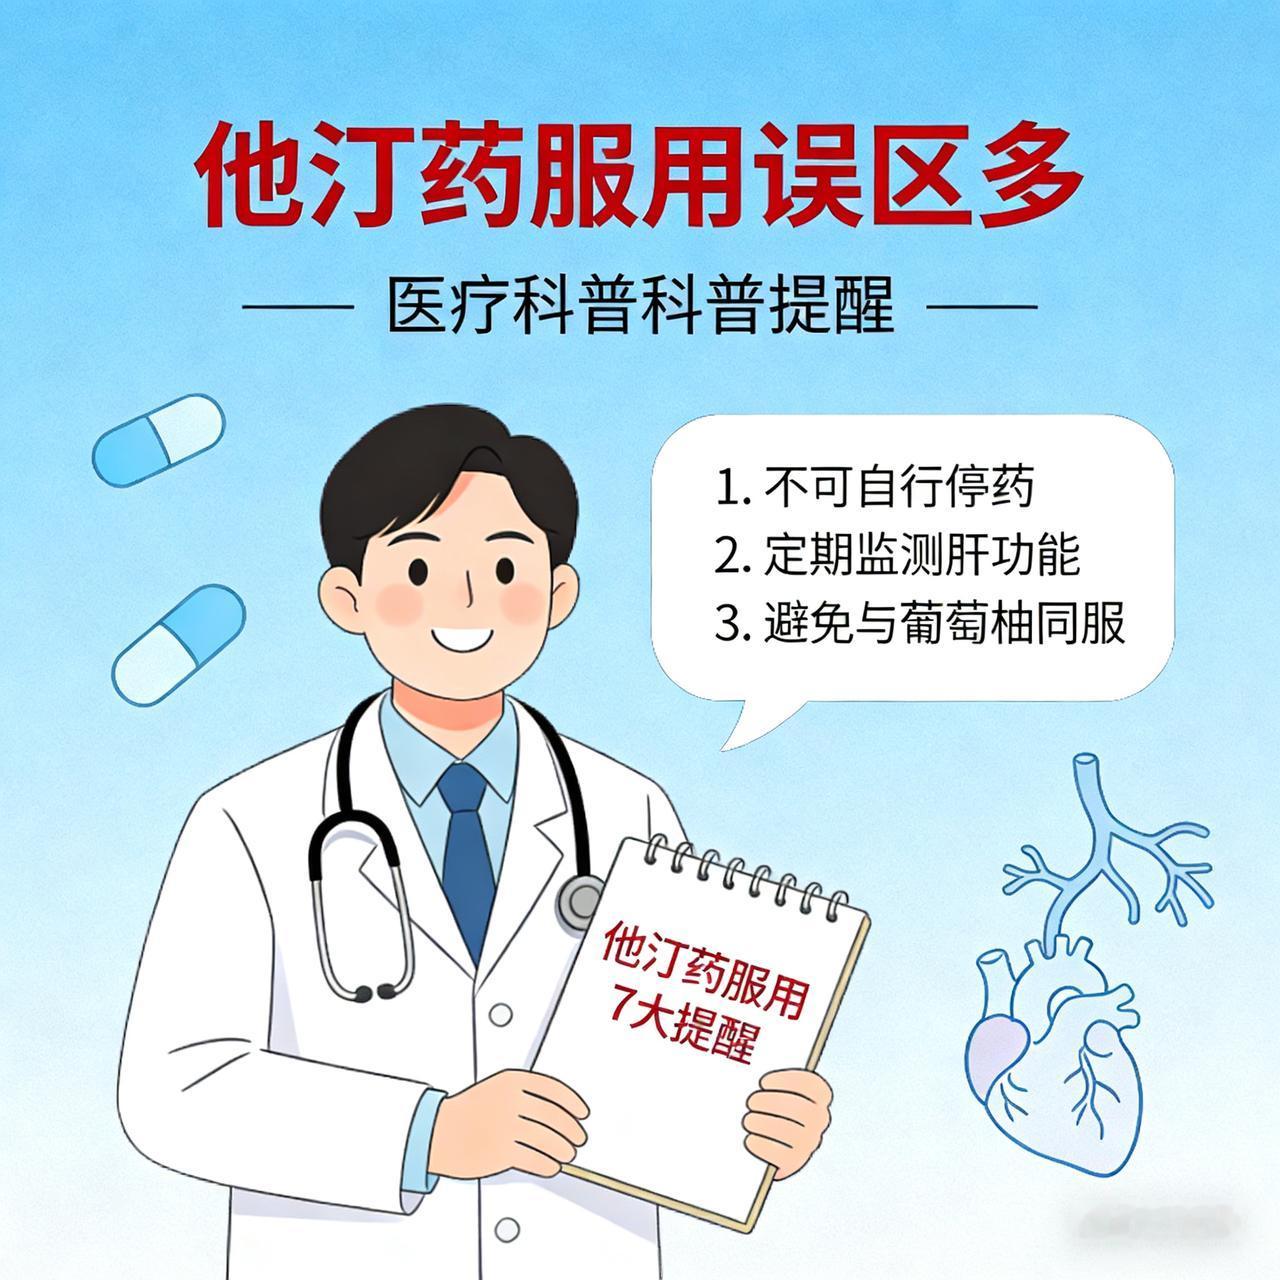

来看看心脏血管斑块破裂是什么样子的。一个 75 岁的男性患者,在医院就诊时,突发心脏骤停倒地,经胸外按压积极抢救后恢复意识。 紧急做了冠状动脉造影,发现是前降支中段一个不稳定斑块出现的破裂,局部有血栓形成。这就是导致患者突发意识丧失的原因。导丝通过前降支病变后,植入支架三枚,把斑块附近的有动脉硬化的血管全部覆盖,血流恢复通畅。 其实这里的狭窄本身并不严重,狭窄程度大约在 70% 左右。突然出现急性心肌梗塞,并不是说堵塞非常严重,而是一些不稳定的斑块突然破裂,导致的局部血栓形成,进而堵塞整个血管。 冠心病的治疗,一方面是预防血栓,另外一方面是尽量稳定动脉硬化斑块,让其不容易破裂。稳定斑块的方法,最主要的是降低低密度脂蛋白胆固醇,一旦发现有冠心病,最好把低密度脂蛋白胆固醇降低到 1.8 以下,最好降低到 1.4 以下。这样斑块才会更加稳定,不容易破裂,也就不容易突发急性心肌梗塞了。